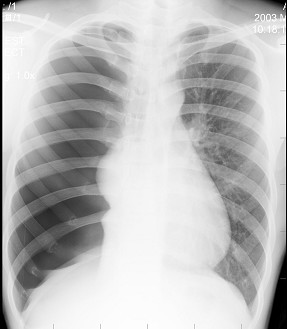

肺气肿的胸片表现,肺气肿胸片典型图片

图1 胸片显示双肺弥漫性浸润,主要在中下肺